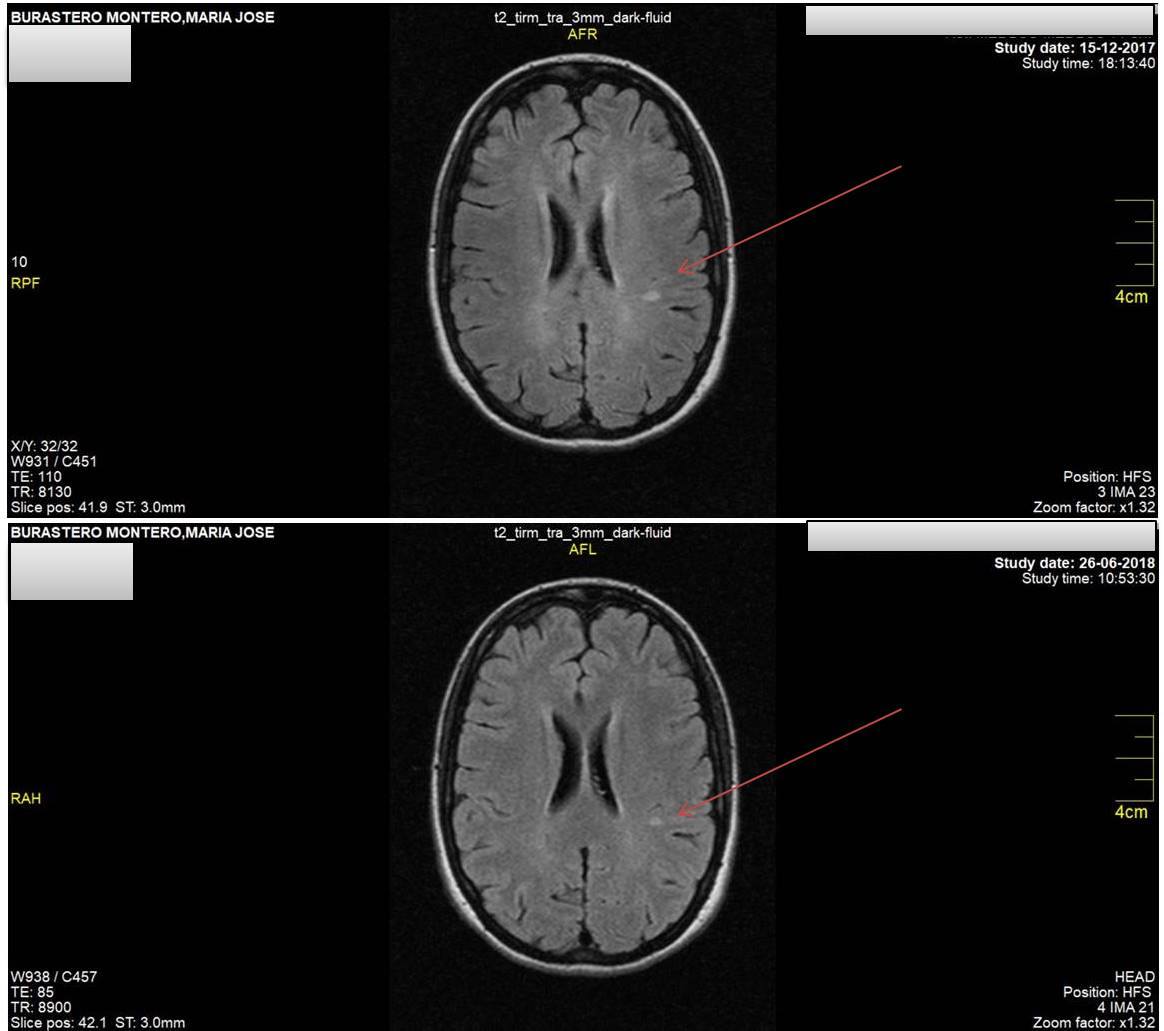

En Octubre 2015 me diagnosticaron esclerosis múltiple. Comencé con lesiones en los pedúnculos cerebelosos medios y C2.

En Mayo 2016 aparecieron más lesiones en la protuberancia y pedúnculo cerebeloso izquierdo.

Enero 2017 aparecieron 3 lesiones nuevas en médula cervical y dorsal.

Diciembre 2017 aparecieron 4 lesiones nuevas: parietal izquierdo, frontal superior derecho, temporal inferior izquierdo, peritrigonal izquierdo (Estas lesiones se produjeron entre Febrero y Septiembre).

Comencé dieta paleo (M. Grez) en Octubre 2017 y Trementina en Marzo 2018.

Los resultados de la última resonancia JUNIO 2018 demostraron que todas las lesiones ocurridas entre 2015 y principios 2017 están eliminadas, tanto del cerebelo como de la médula y algunas del cerebro. Sólo quedan 3 últimas lesiones, que comparando las imágenes están más pequeñas y borrosas.

Les dejo las imágenes para que vean la maravilla que hicieron Dieta + Trementina por mí, y ¡¡¡cómo estoy ya en el último paso de revertir la Esclerosis Múltiple!!!!

Imagen de arriba: Diciembre 2017

Imagen de abajo: Junio 2018